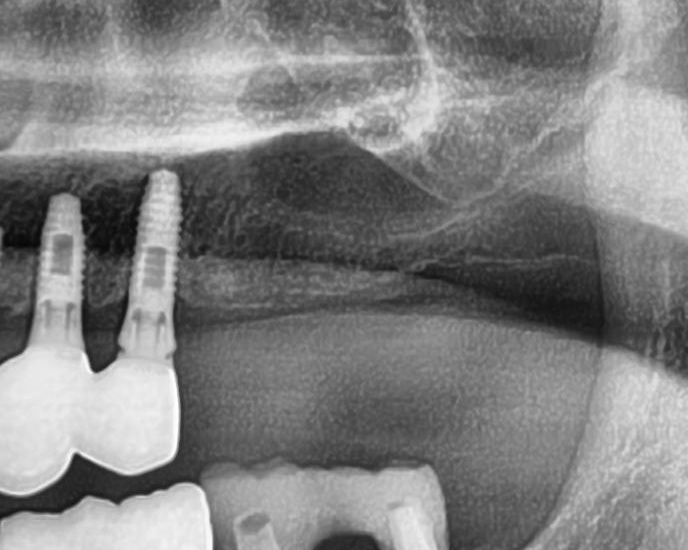

今回の患者様はインプラント植立を希望され、左上5番目・6番目・7番目の3本の植立が決まりました。

しっかりとインプラント埋め込まれた後は、動揺がないか、噛んだ時に当たらないかなどを確認して、最後にパノラマ写真を撮影して今回のオペは終了となりました。